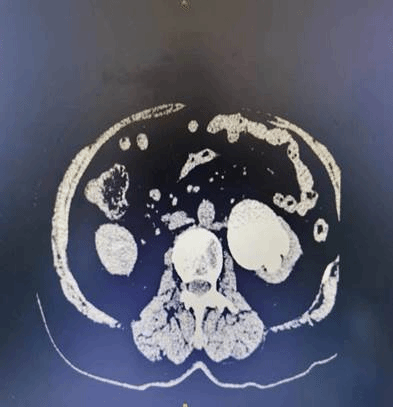

在充分的术前准备后,手术如期进行。机器人臂在医生的操作下灵活飞舞。患者左侧输尿管上段可见两条横跨的血管勒住输尿管,这也是肾盂输尿管狭窄的主因。肾盂输尿管交界处:被勒住的地方狭窄变形。凭借丰富的经验,任明华教授彻底松解勒住的输尿管,对肾盂输尿管给予成形再吻合。患者术后安返病房,第二日便恢复排气,不超过一周便顺利出院。

达芬奇机器人手术图